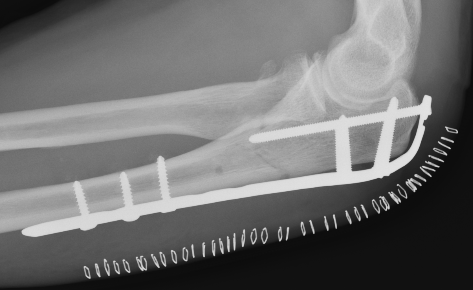

ORIF with olecranon plate

Indication

Fracture distal to center of rotation of elbow / trochlea

Technique

Lateral decubitus with tourniquet

- curvilinear incision to avoid prominence of olecranon

- identify and protect ulna nerve

- reduce fracture with arm in extension

- ensure articular congruity

- use anatomical precontoured plate

- may want to split distal triceps to reduce proximal plate prominence